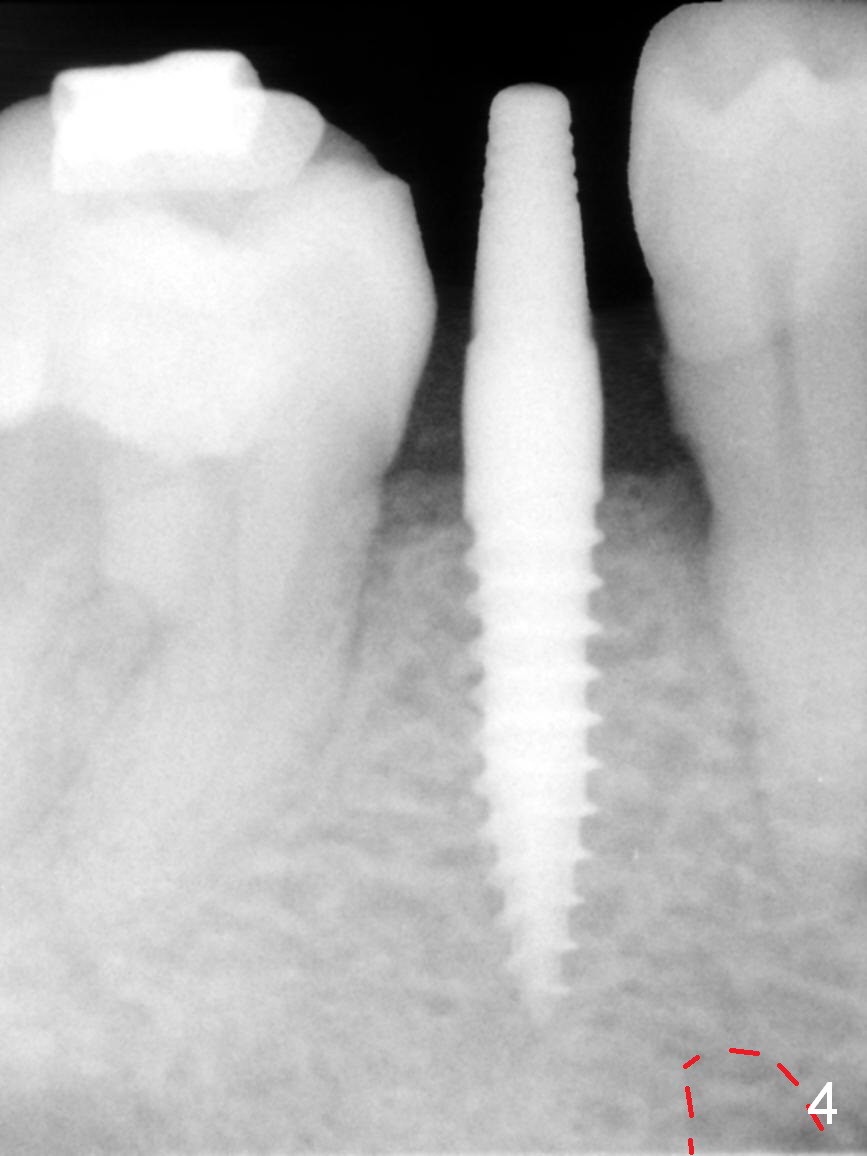

Mesialization of the tooth #29 consists of open coil spring distal (Fig.1 ^) and closed coil spring mesial (^^^). Due to limited time and incompliance, the mesialization is incomplete (Fig.3 *). Total treatment lasts 1 year. The mesial surface of the #29 (Fig.3 <) and the distal surface of #31 are trimmed before incision. The mesiodistal width increases from 5 mm to 6 mm. In fact the ridge is not too narrow buccolingually when an incision is made (Fig.3). There is bone buccal and lingual to a 2.5 mm osteotomy (Fig.3) after adjustment of its initial one with 1.2 mm pilot drill (Fig.2 (red dashed line: the Mental Loop). A 3x12(2) mm 1-piece implant is placed (Fig.4) with insertion torque > 40 Ncm. GBR is also done to increase ridge width.